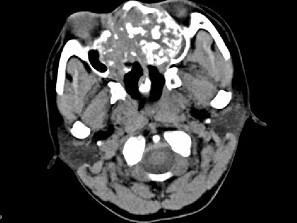

问题 男,26岁,进行性鼻腔阻塞、流涕来院就诊,近两年持续性头痛、头晕.如图所示筛窦区占位灶应诊断为 ( )

选项 A、骨结核伴左上颌窦炎 B、骨纤维异常增殖症伴左上颌窦炎 C、软骨瘤伴左上颌窦炎 D、骨化性纤维瘤伴左上颌窦炎 E、脊索瘤伴左上颌窦炎

答案 C